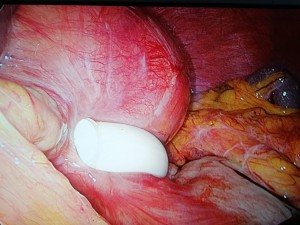

Durante la intervención se objetiva Banda gástrica deslizada con dilatación proximal del estómago sin signos de isquemia ni perforación.

Se realiza retirada de la banda gástrica por vía laparoscópica y el procedimiento transcurre sin incidencias por lo que la paciente es dada de alta al día siguiente de la intervención.